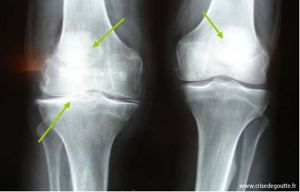

Les radiographies des articulations sont caractéristiques et permettent de diagnostiquer la maladie (1,2).

Radiographie des genoux montrant la présence d'une chondrocalcinose.